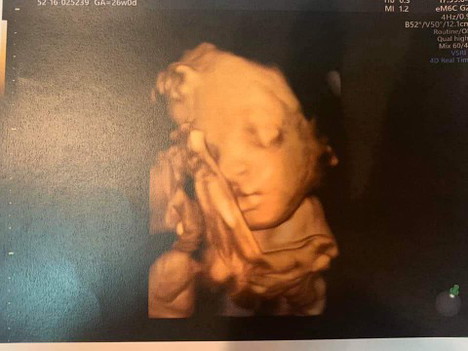

อัลตร้าซาวด์ 4D อายุครรภ์ 6 เดือนครึ่งค่ะ

ผมเป็นเด็กผูชายคับ ผมนอนอย่างเดียว

หม่่ามี๊ of 1 ช่างสงสัย หนุ่มน้อย